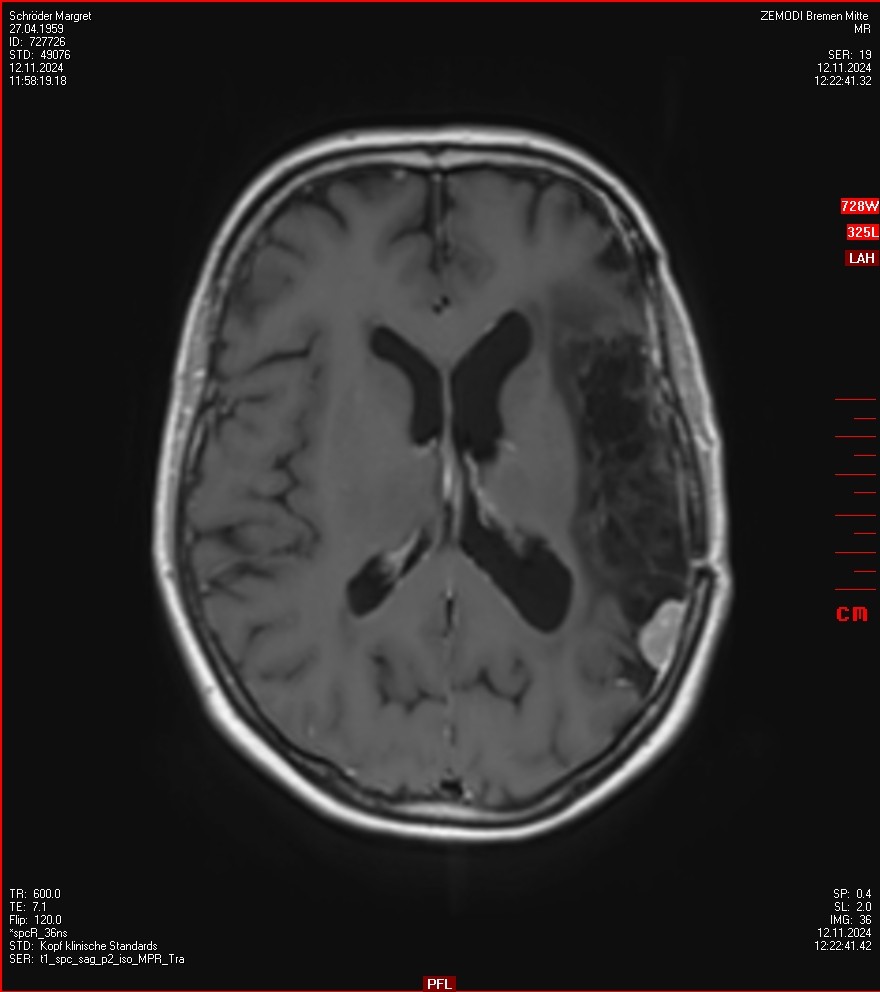

Man bekommt eine CD mit und kann auch für eine Weile online bei Zemodi auf die Bilder zugreifen. Mein Blick auf die Bilder ergibt einen kleinen Schreck. Da scheint allerlei zu wachsen. Nun, ich bin keine Expertin und deshalb froh, dass ich in ein paar Tagen einen Termin bei der Neurochirugie in der Ambulanz des Krankenhaus-Bremen-Mitte habe.

In der Ambulanz der Neurochirurgie im Bremen Krankenhaus-Mitte sind die Bilder interpretiert worden und es ist eine Behandlung nötig. Da wächst ein Menigeom ziemlich nah beim Sehnerv. Alles was im Bild markiert ist, gehört nicht dahin.